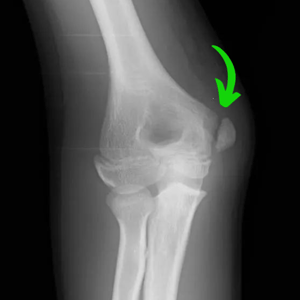

Diagnosis of little league elbow is typically done via clinical examination with a history of throwing and pain on the inside of the elbow. Diagnosis is confirmed via x-ray that shows a small separation of the growth plate on the medial epicondyle.

The most common complication of little league elbow is an avulsion fracture of the medial epicondyle. This is a relatively rare, but significant complication that happens in roughly 16% of little league elbow cases. This is most commonly found in athletes who continued throwing through pain or ignored medical guidance for a period of rest to recover from little league elbow.